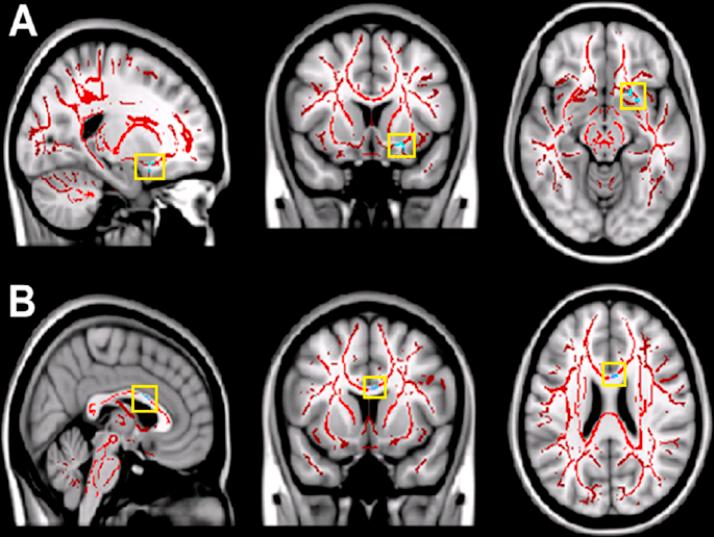

Self-imposed short sleep durations are increasingly commonplace in society, and have considerable health and performance implications for individuals. Reduced sleep duration over multiple nights has similar behavioural effects to those observed following acute total sleep deprivation, suggesting that lack of sleep affects brain function cumulatively. A link between habitual sleep patterns and functional connectivity has previously been observed, and the effect of sleep duration on the brain's intrinsic functional architecture may provide a link between sleep status and cognition. However, it is currently not known whether differences in habitual sleep patterns across individuals are related to changes in the brain's white matter, which underlies structural connectivity. In the present study we use diffusion-weighted imaging and a group comparison application of tract based spatial statistics (TBSS) to investigate changes to fractional anisotropy (FA) and mean diffusivity (MD) in relation to sleep duration and quality, hypothesising that white matter metrics would be positively associated with sleep duration and quality. Diffusion weighted imaging data was acquired from a final cohort of 33 (23-29 years, 10 female, mean 25.4 years) participants. Sleep patterns were assessed for a 14 day period using wrist actigraphs and sleep diaries, and subjective sleep quality with the Pittsburgh Sleep Quality Index (PSQI). Median splits based on total sleep time and PSQI were used to create groups of shorter/longer and poorer/better sleepers, whose imaging data was compared using TBSS followed by post-hoc correlation analysis in regions identified as significantly different between the groups There were significant positive correlations between sleep duration and FA in the left orbito-frontal region and the right superior corona radiata, and significant negative correlations between sleep duration and MD in right orbito-frontal white matter and the right inferior longitudinal fasciculus. Improved sleep quality was positively correlated with FA in left caudate nucleus, white matter tracts to the left orbito-frontal region, the left anterior cingulum bundle and the white matter tracts associated with the right operculum and insula, and negatively correlated with MD in left orbito-frontal white matter and the left anterior cingulum bundle. Our findings suggest that reduced cumulative total sleep time (cTST) and poorer subjective sleep quality are associated with subtle white matter micro-architectural changes. The regions we identified as being related to habitual sleep patterns were restricted to the frontal and temporal lobes, and the functions they support are consistent with those which have previously been demonstrated as being affected by short sleep durations (e.g., attention, cognitive control, memory). Examining how inter-individual differences in brain structure are related to habitual sleep patterns could help to shed light on the mechanisms by which sleep habits are associated with brain function, behaviour and cognition, as well as potentially the networks and systems responsible for variations in sleep patterns themselves.

自我设定的短睡眠时间在社会中越来越普遍,对个人的健康和表现有相当大的影响。多个晚上睡眠时长减少所产生的行为影响,与急性完全睡眠剥夺后观察到的影响相似,这表明睡眠不足会累积影响大脑功能。此前已观察到习惯性睡眠模式与功能连接之间存在联系,而睡眠时间对大脑内在功能结构的影响可能为睡眠状态与认知之间提供一种联系。然而,目前尚不清楚个体之间习惯性睡眠模式的差异是否与大脑白质的变化有关,而白质是结构连接的基础。在本研究中,我们使用扩散加权成像和基于束的空间统计学(TBSS)的组间比较应用,来研究分数各向异性(FA)和平均扩散率(MD)与睡眠时间和质量相关的变化,假设白质指标与睡眠时间和质量呈正相关。扩散加权成像数据是从33名(年龄在23 - 29岁之间,10名女性,平均25.4岁)参与者的最终队列中获取的。使用腕部活动记录仪和睡眠日记对睡眠模式进行了为期14天的评估,并使用匹兹堡睡眠质量指数(PSQI)评估主观睡眠质量。基于总睡眠时间和PSQI的中位数分割用于创建短/长睡眠者和差/好睡眠者组,对他们的成像数据使用TBSS进行比较,随后在组间差异显著的区域进行事后相关分析。睡眠时间与左侧眶额区域和右侧放射冠上部的FA之间存在显著正相关,而睡眠时间与右侧眶额白质和右侧下纵束的MD之间存在显著负相关。睡眠质量改善与左侧尾状核、连接至左侧眶额区域的白质束、左侧前扣带回束以及与右侧岛盖和脑岛相关的白质束中的FA呈正相关,与左侧眶额白质和左侧前扣带回束中的MD呈负相关。我们的研究结果表明,累积总睡眠时间(cTST)减少和主观睡眠质量较差与白质微观结构的细微变化有关。我们确定的与习惯性睡眠模式相关的区域局限于额叶和颞叶,它们所支持的功能与先前已证明受短睡眠时间影响的功能(如注意力、认知控制、记忆)一致。研究大脑结构的个体差异如何与习惯性睡眠模式相关,有助于阐明睡眠习惯与大脑功能、行为和认知相关的机制,以及潜在地揭示负责睡眠模式变化的网络和系统。